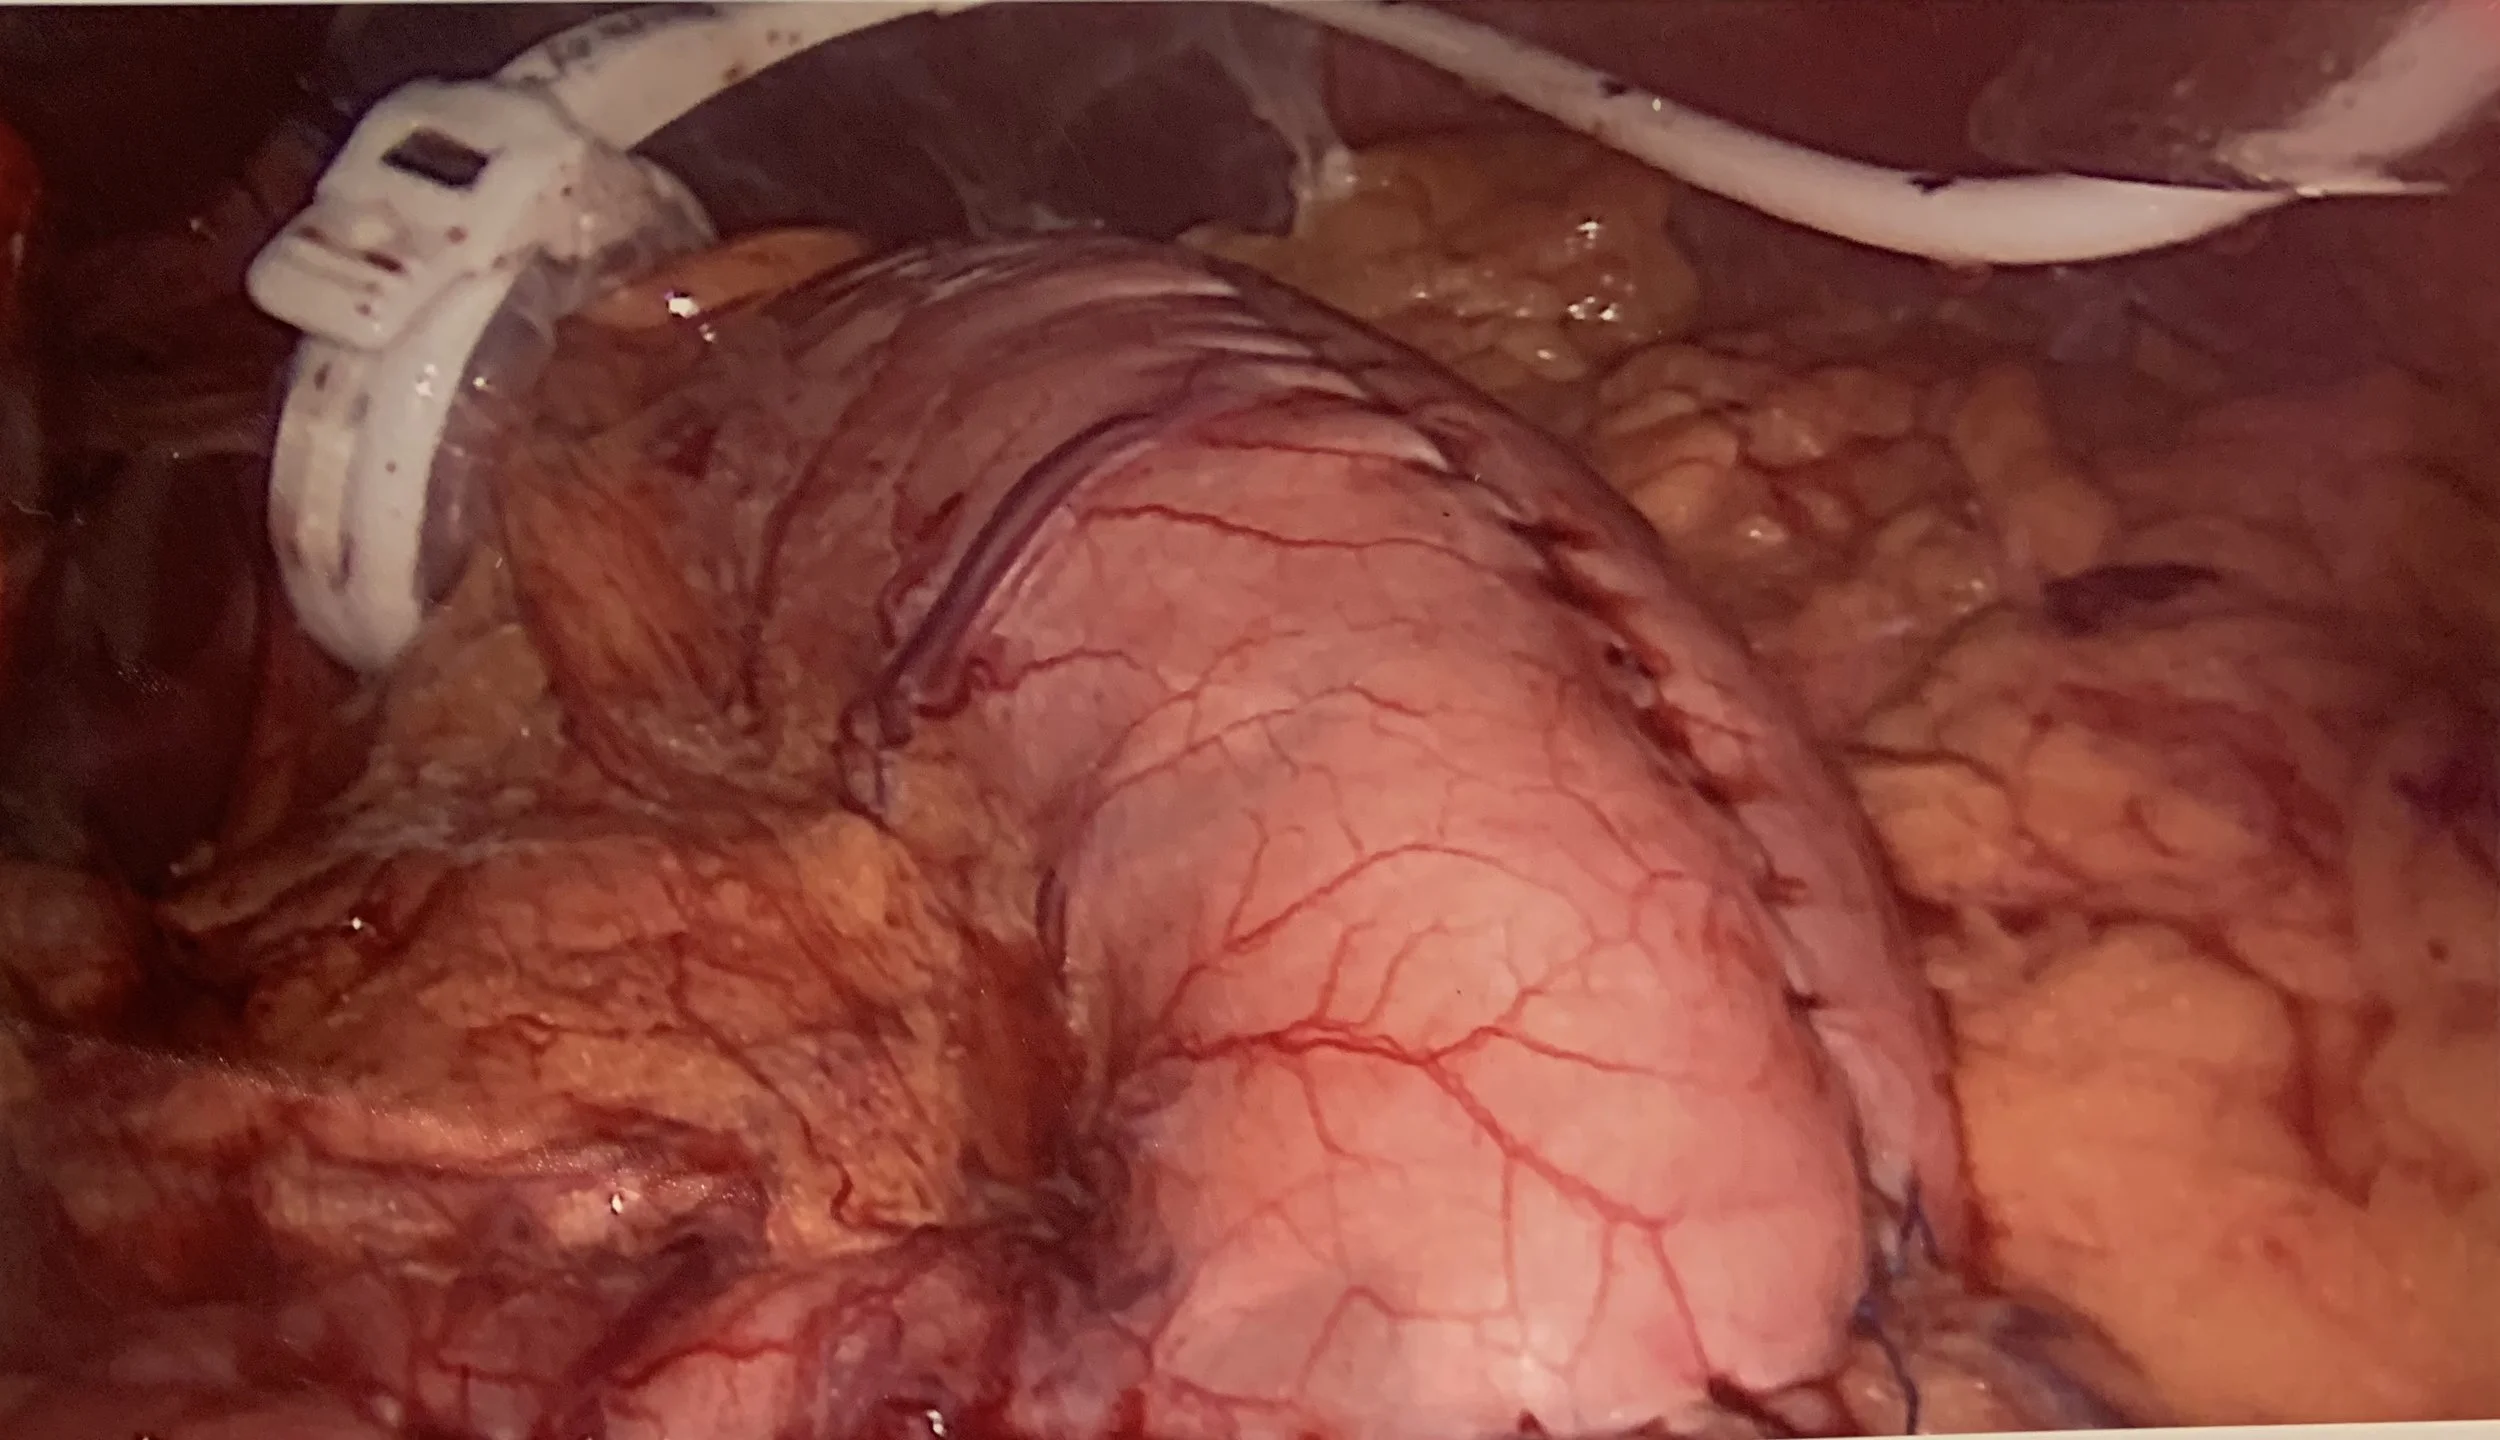

The gastric plication can be performed alone or with the gastric band and consist of:

1. gastric plication

- the stomach volume is reduced by suturing techniques, without any resection

- potentially reversible

My recent modification in the technique consists of a fat, omental imbrication which, in theory makes the stomach full when you are overweight and more roomy when you lose weight. It also preserves the gastro-epiploic blood supply reducing the risk of stomach necrosis. Theoretically it gives the stomach the ability to adjust its’ volume depending on your weight, which means you can eat more when you lose weight and less if you gain.